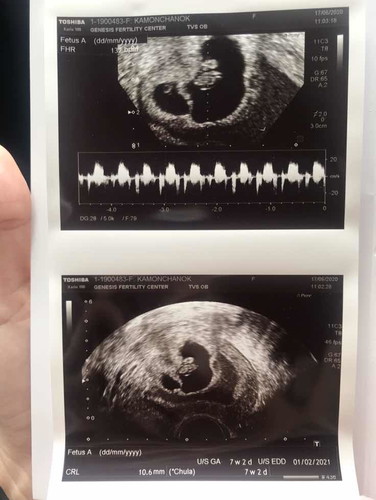

ขนาดตัวอ่อน

สวัสดีค่ะ มีแม่คนไหนอัลตราซาวด์ ตอน7 วีค5วัน พบหัวใจน้องเต้นปกติ แต่น้องมีตัวอ่อนเล็กกว่าเกณฑ์ 3วันบ้างค่ะ